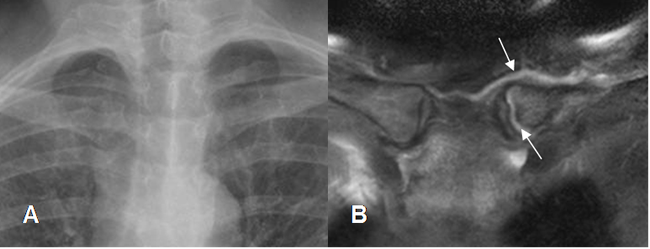

Fig 31B. Cambios degenerativos.

A: Rx PA. No se encuentran anormalidades.

B: RM coronal en STIR. Escaso líquido dentro y rodeando la articulación esternoclavicular, por cambios degenerativos incipientes.